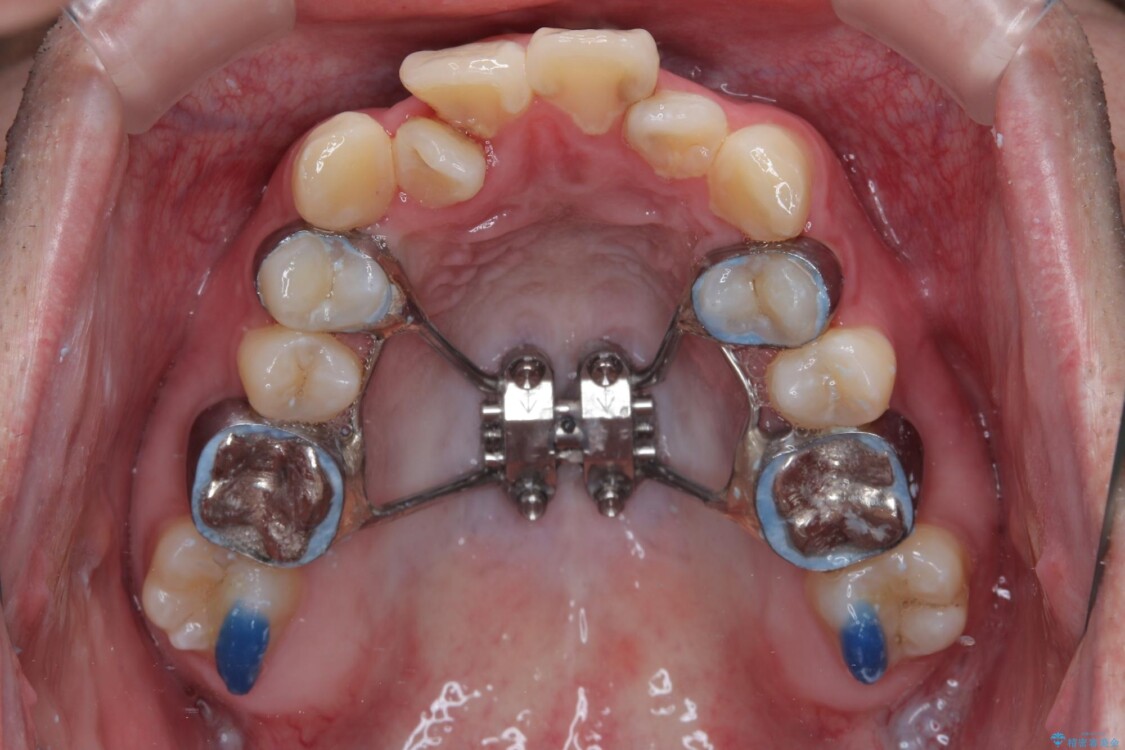

治療方針

このような歯列の狭さに起因するデコボコを改善するために、**MARPE(骨に固定する上顎急速拡大装置)**を使用して、上顎の横幅を拡大し、これにより歯が並ぶためのスペースを確保し、メタルブラケットを用いて歯列を整えていく計画としました。

治療途中

• 1年でここまで変わる!歯列のがたつきと正中のズレを改善した矯正治療(メタルブラケット×MARPE) 治療途中画像